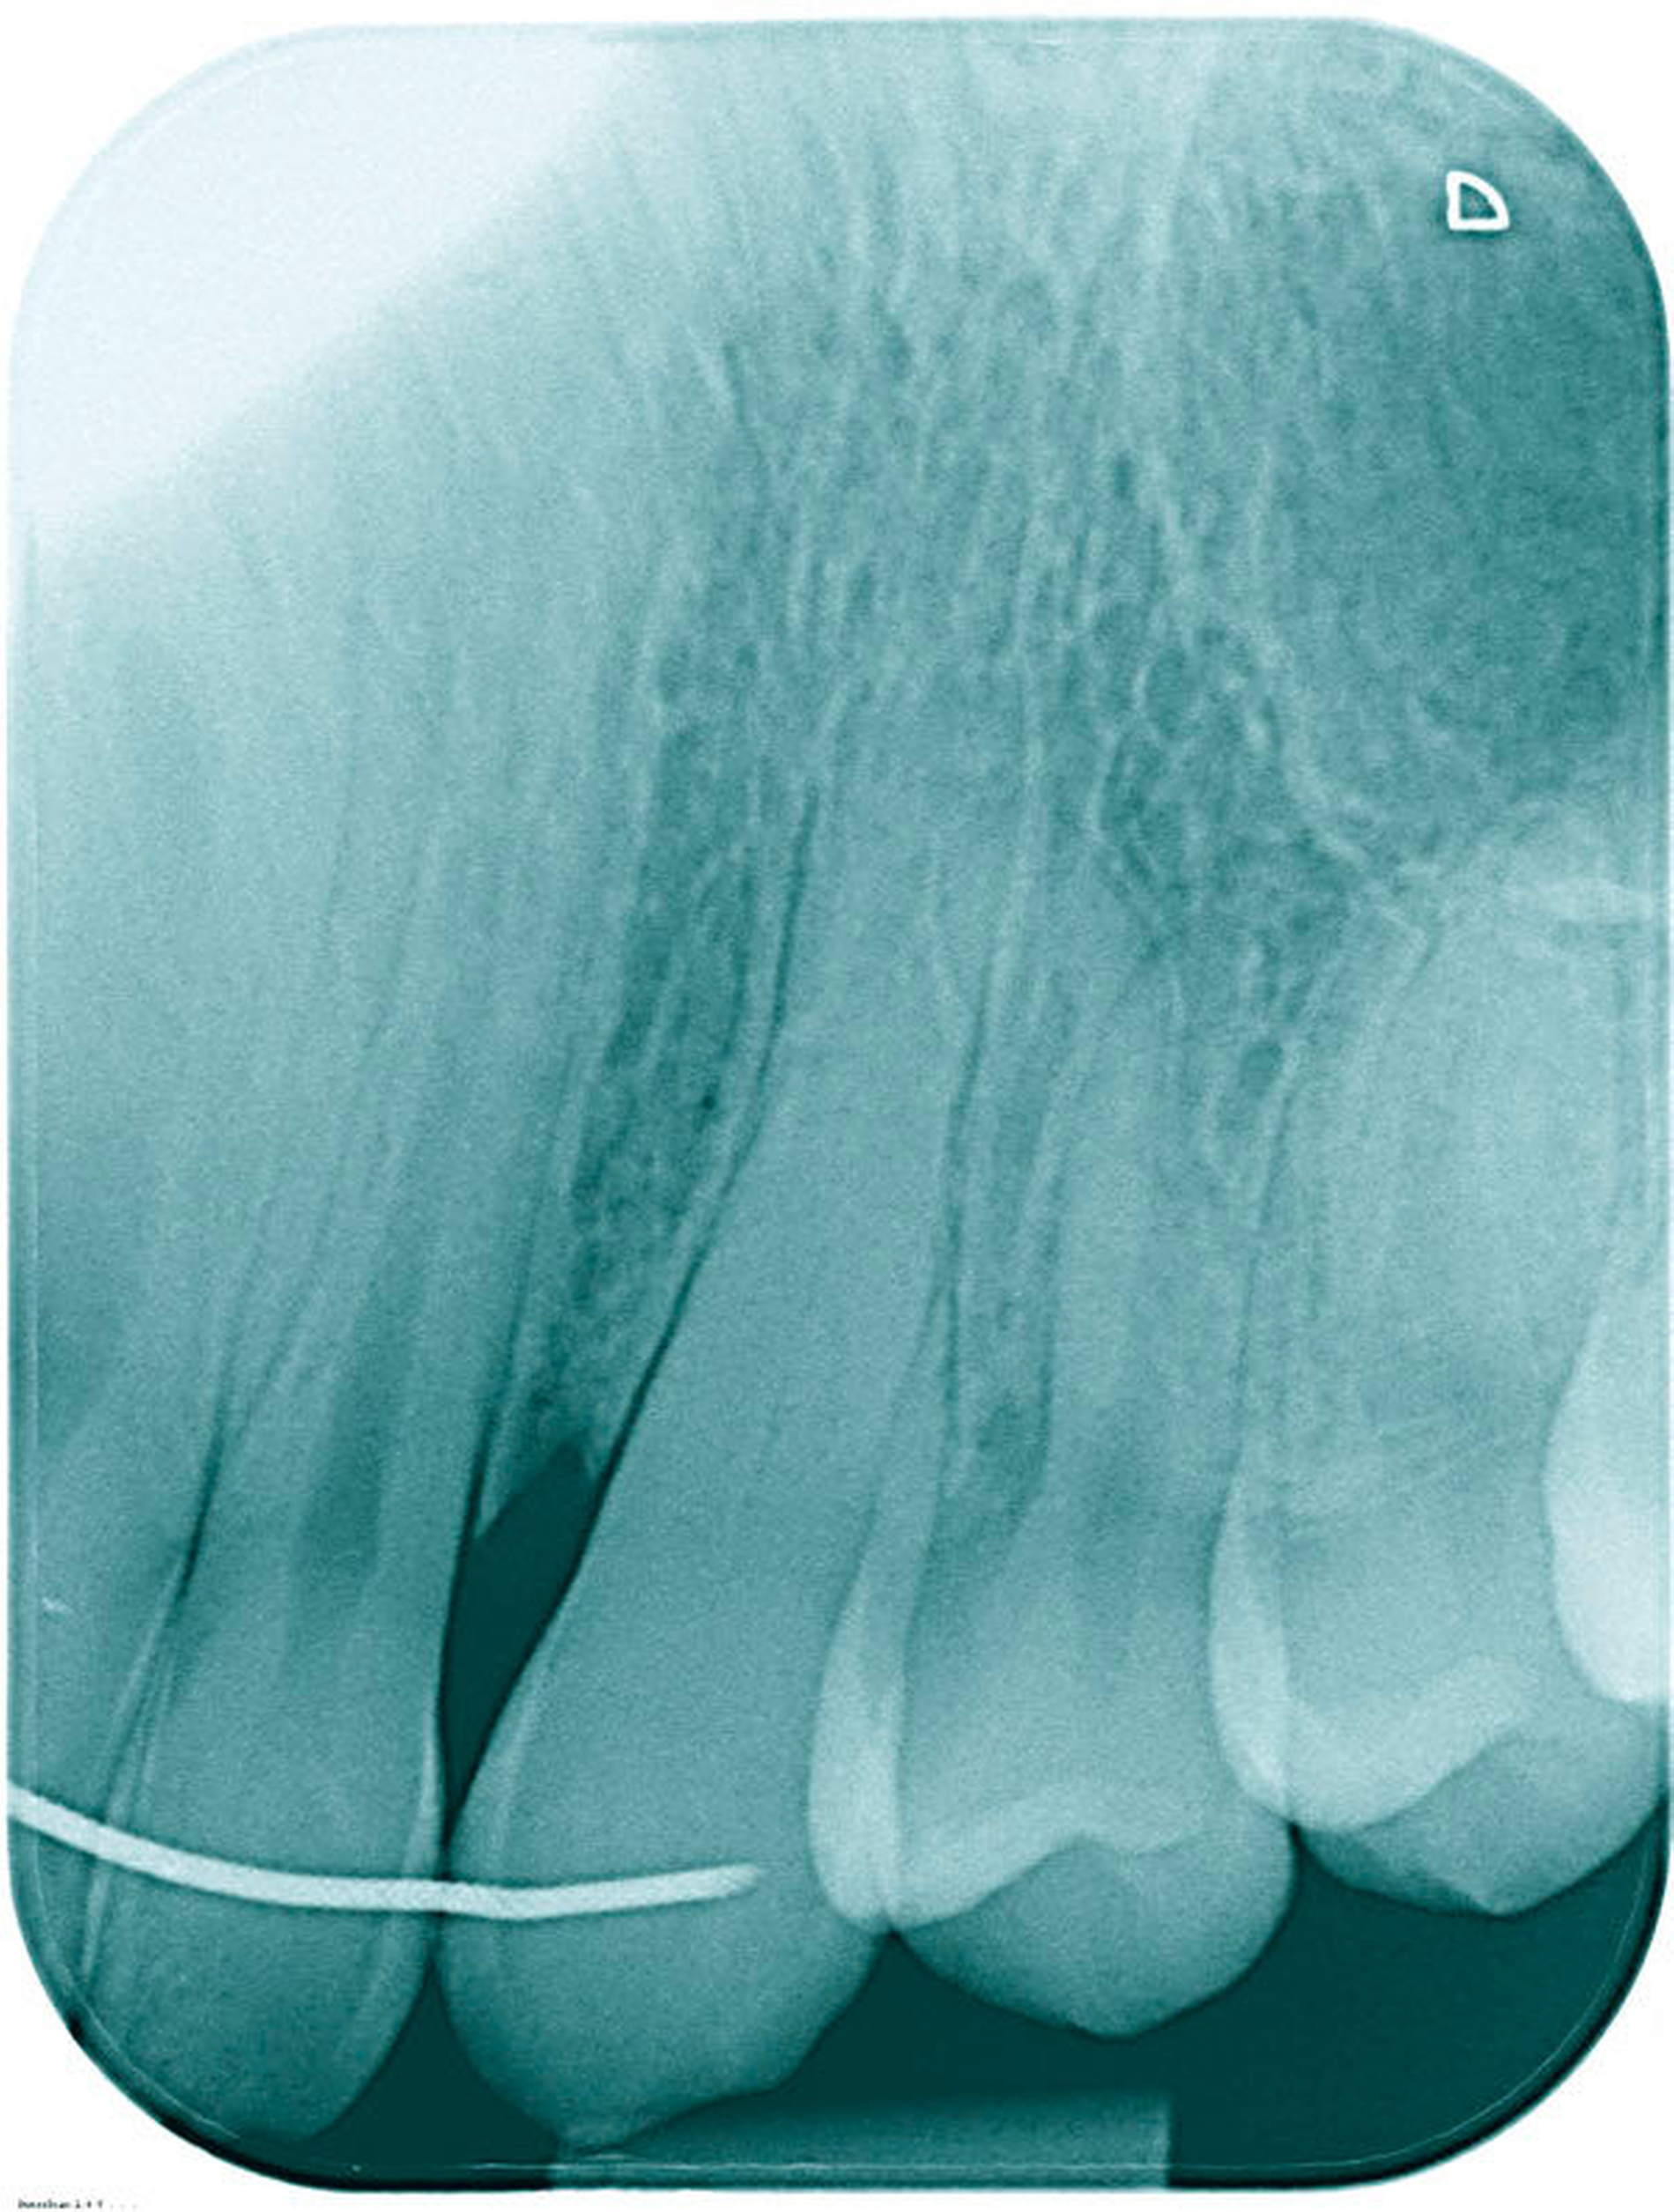

Der 17-jährige Patient stellte sich mit nicht auffindbarem Wurzelkanal Zahn 23 vor. Er war allgemeinanamnestisch unauffällig. Zum Zeitpunkt der Überweisung war die Trepanation bereits erfolgt und der Zahn provisorisch gefüllt. Ein präoperatives Röntgenbild, auf dem keinerlei Kanalstrukturen erkennbar waren (Abbildung 1) sowie ein OPTG (Abbildung 2) lagen vor. Der Patient klagte über spontanen Schmerz, der Zahn war perkussionsempfindlich, reagierte nicht auf den Kältetest. Der Klopfschall war unauffällig, der vestibuläre Knochen im apikalen Bereich druckschmerzhaft. Die Diagnose lautete symptomatische apikale Parodontitis.

Es erfolgte die Inspektion unter dem OP-Mikroskop. Klinisch zeigte sich kein Anhalt auf Kanalstrukturen. Es erfolgten zwei zeitintensive Sitzungen, in denen der Wurzelkanal nicht dargestellt werden konnte und der Zahn, trotz größter Vorsicht und Verwendung des Mikroskops, perforiert wurde. Die Perforation war vestibulär im mittleren Kanaldrittel nach einer Länge von 18 mm lokalisiert (Abbildungen 3 und 4). Die Therapieentscheidung fiel daraufhin zugunsten einer „Guided Endodontics“-Behandlung.